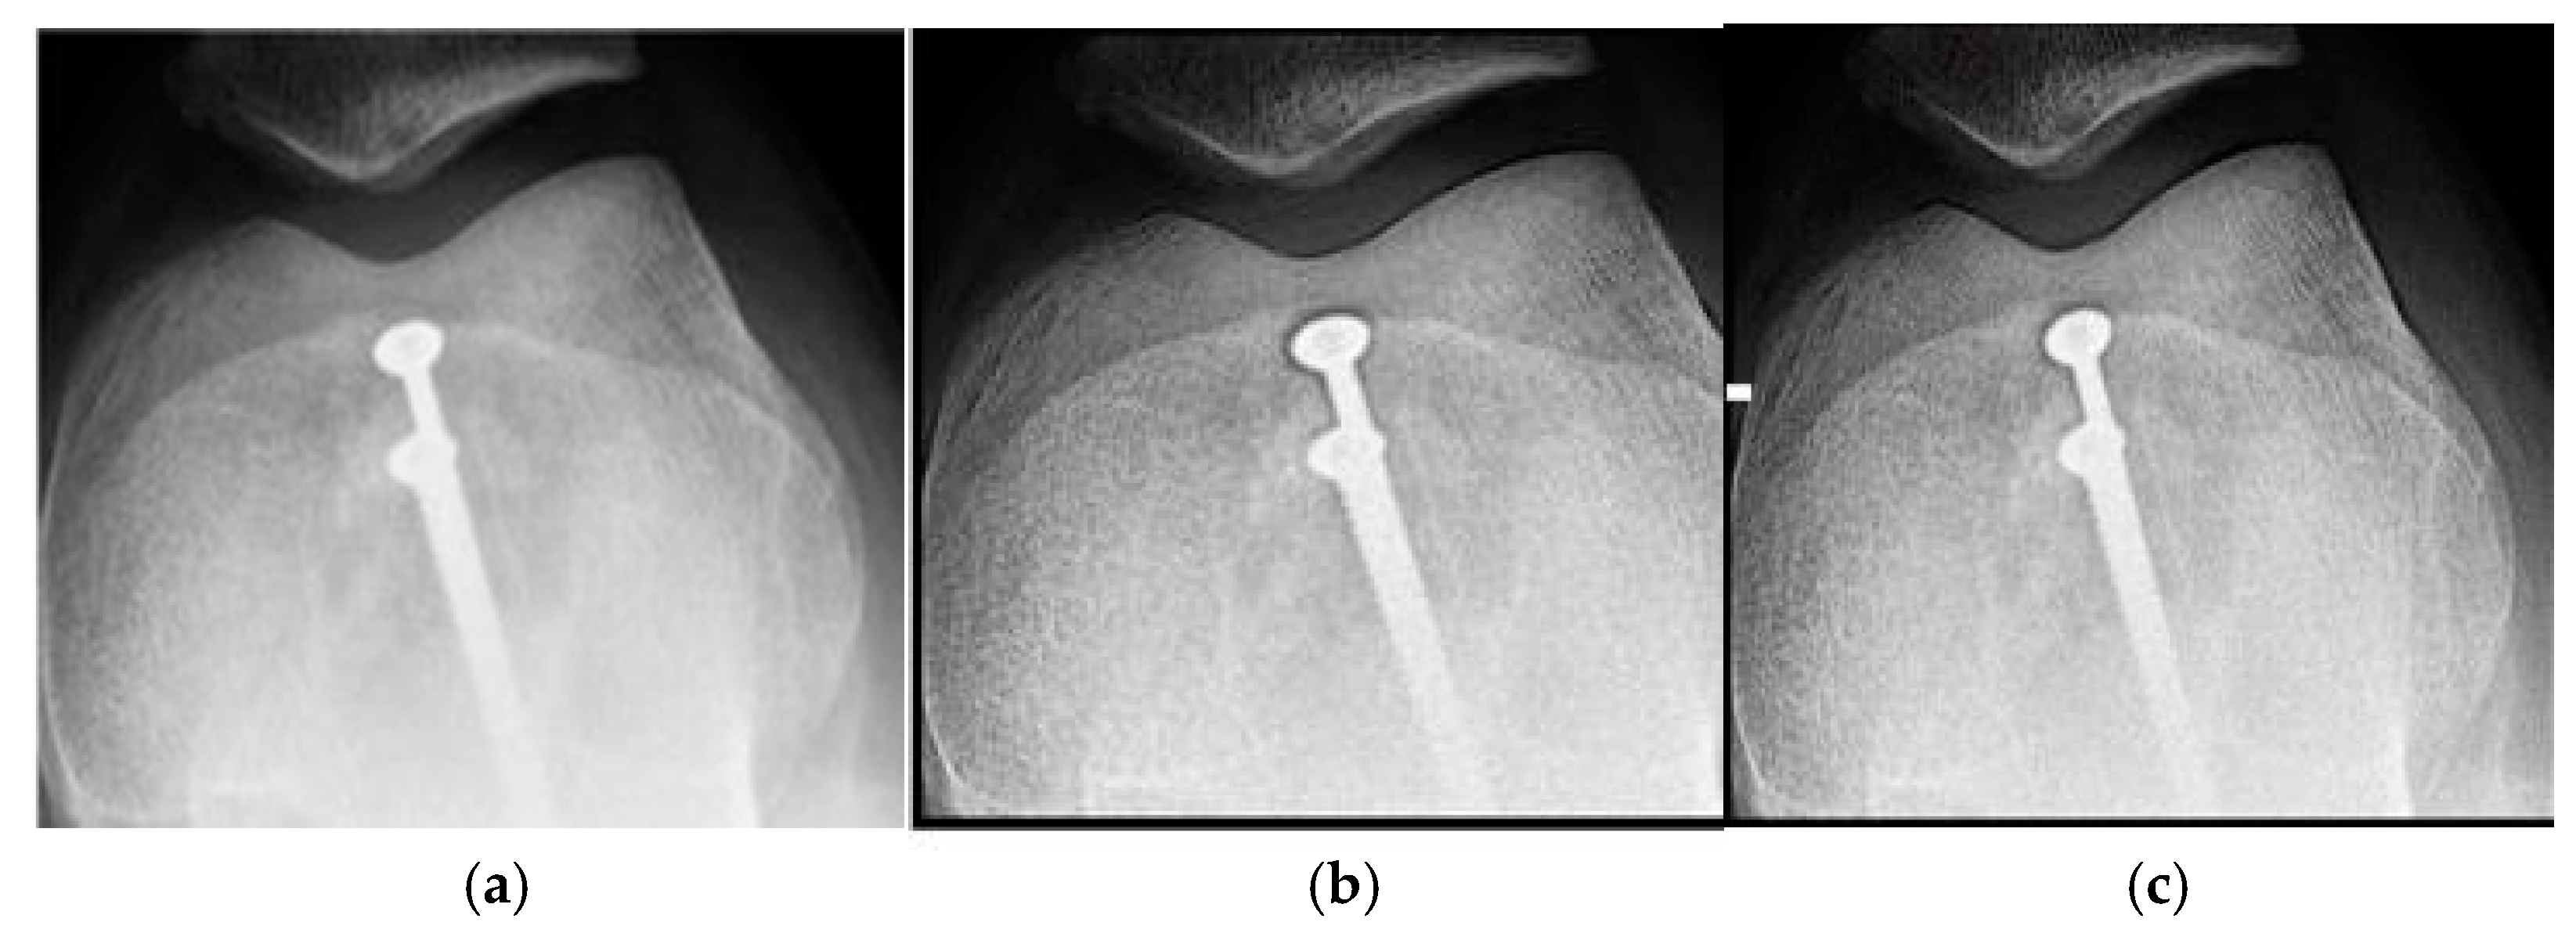

Figure 1a shows the original image of a knee radiograph, which serves as a reference for comparing the effects of the applied filters. Figure 1b shows the image processed with the Cream filter and d = 1.4, which shows improved contrast and sharpness due to reduced scattering and improved bone architecture. Figure 1c shows the image processed with the Bosso filter (d = 1.4), which smooths noise and improves edge definition, resulting in a clearer and more detailed image.

Figure 1. Knee images (a) original, (b) processed with the Cream filter, (c) processed with the Bosso filter.